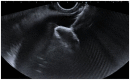

Introduction: The minimally invasive approach of endoscopic ultrasound (EUS)-guided procedures for cholecystocholedocholithiasis, such as EUS-guided gallbladder drainage (EUS-GBD), EUS-guided rendezvous (EUS-RV), and EUS-guided biliary drainage (EUS-BD), is affirmed as an effective treatment for patients with acute cholecystitis (AC) who are unfit for surgery and for patients with common bile duct stones (CBDSs) who have experienced a previous ERCP failure. Furthermore, in cases of difficult CBDS extraction during endoscopic retrograde cholangiopancreatography (ERCP), cholangioscopy-guided electrohydraulic lithotripsy (CS-EHL) has showed optimal results. The main objective of our study was to evaluate the effectiveness of EUS-GBD and percutaneous gallbladder drainage (PT-GBD) in patients with AC who are unfit for surgery. We also aimed to evaluate the efficacy of EUS-GBD, EUS-BD, and EUS-RV following ERCP failure and the effectiveness of CS-EHL for difficult CBDS extraction in our hospital. The secondary aim was to examine the safety of these procedures.

Materials and methods: We conducted a retrospective evaluation of all the EUS-GBD, PT-GBD, EUS-BD, EUS-RV, and CS-EHL procedures, which were prospectively collected in the gastroenterology and digestive endoscopy unit and the general surgery unit from January 2020 to June 2023. The efficacy was expressed in terms of technical and clinical success rates, while safety was assessed based on the rate of adverse events (AEs).

Results: We enrolled 83 patients with AC and high surgical risk. Among them, 57 patients (68.7%, 24/57 male, median age 85 ± 11 years) underwent EUS-GBD, and 26 (31.3%, 19/26 male, median age 83 ± 7 years) underwent PT-GBD. The technical and clinical success rates were 96.5 and 100% for EUS-GBD, and 96.1 and 92% for PT-GBD. The AEs for EUS-GBD were 1.7%, and for PT-GBD, it was 12%. ERCP for CBDS extraction failed in 77 patients. Among them, 73 patients (94.8%) underwent EUS-RV with technical and clinical success rates of 72.6% (53/73) and 100%, respectively. No AEs were reported. Four out of 77 patients were directly treated with EUS-BD for pyloric inflammatory stenosis. In 12 patients (16.4%), following unsuccessful EUS-RV with a CBD diameter ≥ 12 mm, an EUS-BD was performed. Both technical and clinical success rates for EUS-BD were 100%, and no AEs were reported. EUS-GBD was the treatment of choice for the remaining 8 (10.9%) patients after failure of both ERCP and EUS-RV. The procedure had high technical and clinical success rates (both at 100%), and no AEs were reported. The 12 difficult CBDS extraction treated with CS-EHL also showed high technical and clinical success rates (both at 100%), with no reported AEs.